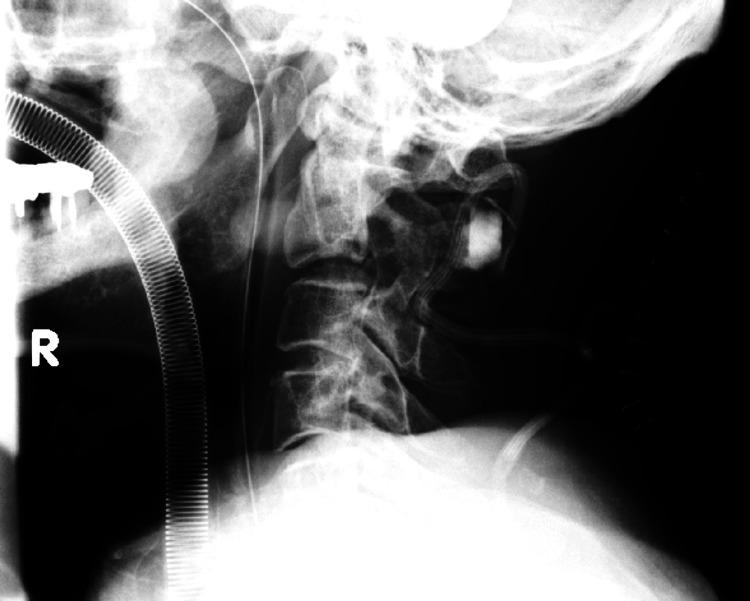

Traumatic herniations of the upper cervical spine are rare, with a higher likelihood of occurrence in older individuals. Their associated neurological symptoms can vary widely, often leading to delays in clinical diagnosis. We report the case of an 86-year-old man who developed neurological symptoms after a fall. Initially, intracranial pathology was suspected, and a head magnetic resonance imaging (MRI) revealed small chronic subdural hematomas, which were managed conservatively. However, as his paralysis progressed over the following days, a repeat brain CT showed no significant changes. Suspecting cervical spine involvement, further imaging identified a C2/3 disc herniation. The patient underwent emergency cervical laminoplasty, but postoperative subluxation required additional surgery, including C1-3 posterior fusion and C2/3 anterior fusion. Post-surgery, the patient exhibited improvement in paralysis affecting both the upper and lower extremities and a reduction in sensory deficits. Early diagnosis and treatment are crucial to improve neuropathic outcomes. A thorough understanding of the symptoms and characteristics of neurological damage to the upper cervical spine can significantly contribute to favorable results. Clinicians should be well-acquainted with this pathological condition.